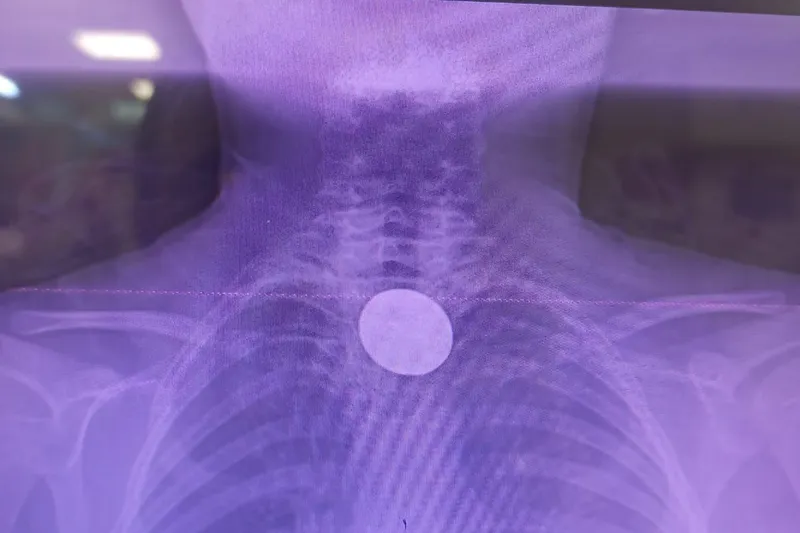

Siirt’te yaşayan 8 yaşındaki Y.K., boğazına madeni para kaçması sonucu ailesi tarafından Siirt Eğitim ve Araştırma Hastanesi’ne götürüldü. Yabancı cisim yutma şikâyetiyle acil servise başvuran küçük hasta, yapılan ilk muayene ve görüntüleme tetkiklerinin ardından hızla değerlendirmeye alındı.

Madeni paranın yemek borusuna kadar indiği tespit edildi

Yapılan incelemelerde 5 TL’lik madeni paranın Y.K.’nin yemek borusuna kadar ilerlediği belirlendi. Çocuk hastalarda ciddi solunum ve sindirim sistemi riskleri oluşturabilen bu durum üzerine ilgili branşlar vakit kaybetmeden harekete geçti.